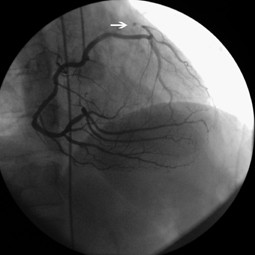

Single coronary artery presenting with ST-segment elevation myocardial infarction

Video 1. Right anterior oblique view shows that left main coronary artery originating from the proximity of the RCA and tracking an unusal direction to the left side and dividing into left anterior descending and left circumflex artery and LCx artery was totally occluded just after the division (avi 0,6MB)